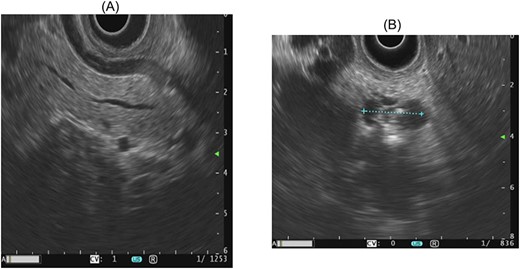

At the presentation in 2021, ultrasonography diagnosed a gallbladder hydrops, but no cause could be delineated for this. Therefore, an MRI with MRCP was performed again leading to the diagnosis of a progressive side branch IPMN with possible focal involvement of the main duct and partial irregular cystic changes, as shown in Fig. 1. Additionally, an endosonography of the pancreas was carried out revealing the image morphology of a combined IPMN involving the main duct and showing progressive side branches with worrisome features shown in Fig. 2. The case was discussed in our multidisciplinary tumor board recommending the evaluation for a pancreatectomy due to high-risk IPMN.

Endosonographic image morphology of a main duct IPMN, as well as progressive side branches with worrisome features, including dilatation of the main pancreatic duct and abrupt changes in the diameter.